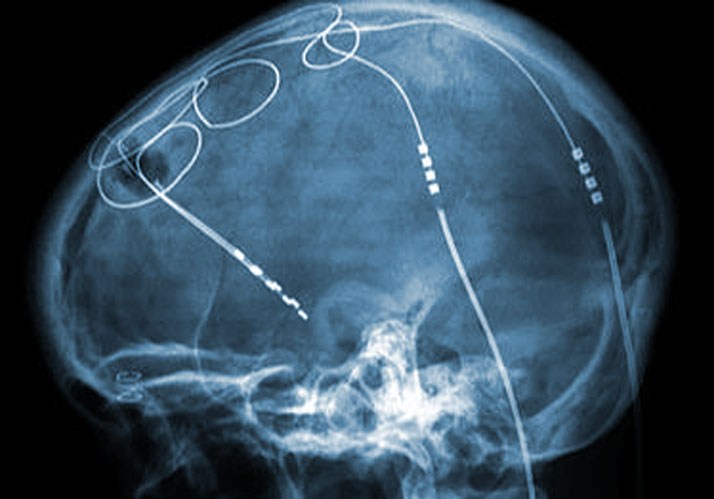

Die Tiefe Hirnstimulation ist eine inzwischen etablierte Methode zur Behandlung der Parkinson-Krankheit und anderer schwerer Bewegungsstörungen. Seit fast 20 Jahren wird Tiefe Hirnstimulation auch zur Behandlung nahezu jeder Art von schweren psychiatrischen Erkrankungen erprobt. Das Spektrum umfasst Zwangsstörungen, Depressionen, Angststörungen, Alkoholsucht, Opiatsucht, Adipositas, Anorexia nervosa, Schizophrenie u.a. Seit einigen Jahren experimentieren zwei konkurrierende Forschergruppen in Deutschland und Kanada auch mit Demenz-Patienten. Echte Erfolge sind bisher ausgeblieben, Komplikationen dagegen nicht. Diese risikoreichen Experimente sind wissenschaftlich und ethisch besonders problematisch. Denn einerseits sind Demenzpatienten aufgrund ihrer hoffnungslosen Situation besonders anfällig für technologische Heilsversprechen. Andererseits können sie aufgrund ihrer Krankheit kaum die Risiken und Chancen angemessen abwägen.

Bildquelle: Wikimedia Commons/Craig Hacking, Frank Gaillard